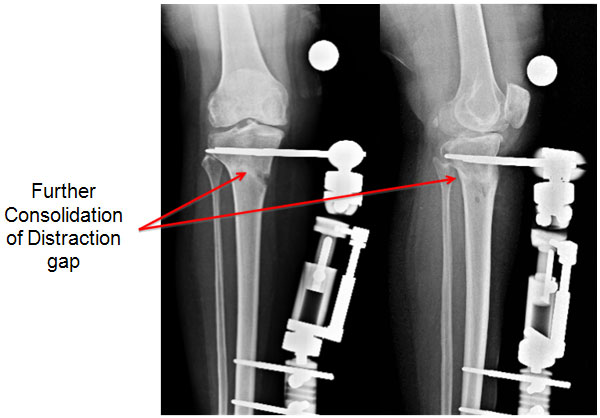

| 10 weeks |

| |